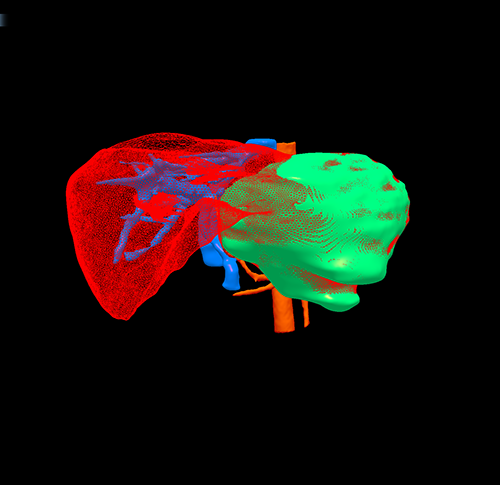

三维重建

左肝癌--左半肝切除